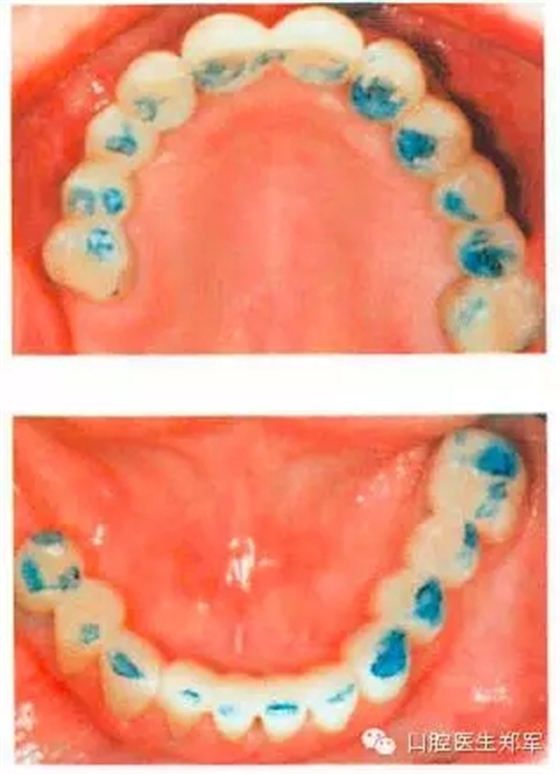

治療選擇:正畸治療(Hawley矯治器)+ 舌面金屬絲加復(fù)合材料的夾板防止復(fù)發(fā)。Hawley矯治器可以分離上、下后牙,前牙的橡皮圈或金屬絲可以使下前牙內(nèi)收,同時使上前牙恢復(fù)到牙列的正常位置(圖6)。

圖6:用橡皮筋和固定托槽來使外展的上下前牙內(nèi)收。依靠復(fù)合材料粘接覆蓋到尖牙上來抬高垂直空間。下頜前牙內(nèi)收后為上頜前牙的內(nèi)收提供空間。